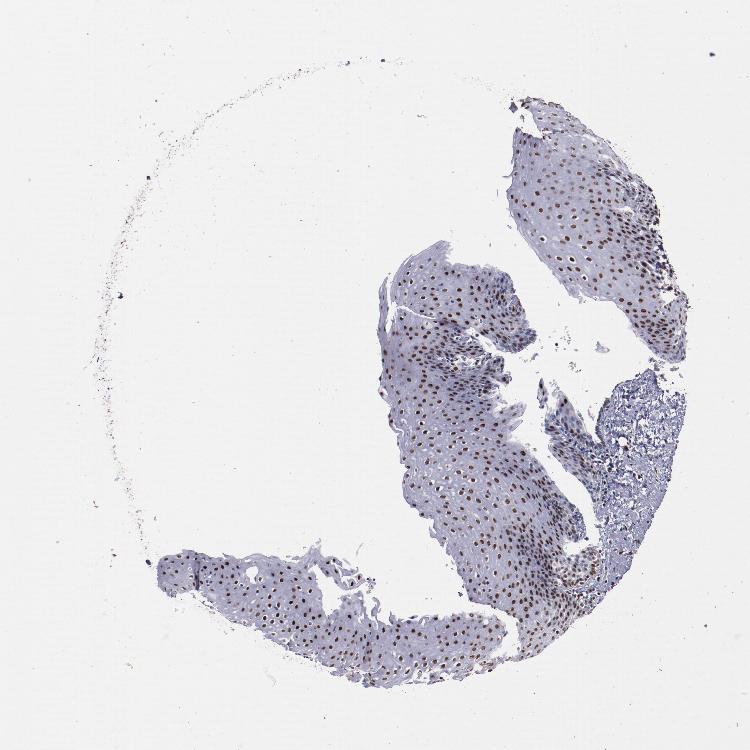

ESOPHAGUS - Antibody stainingi

Antibody staining in the annotated cell types in the current human tissue is reported as not detected, low, medium, or high, based on conventional immunohistochemistry profiling in selected tissues. This score is based on the combination of the staining intensity and fraction of stained cells.

Each image is clickable and will lead to virtual microscopy that enables deeper exploration of all samples and also displays staining intensity scores, fraction scores and subcellular localization as well as patient and tissue information for each sample.

Antibody HPA002568

Squamous epithelial cells High